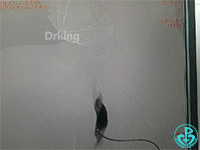

行冠脉造影,从肱动脉开始泥鳅导丝一直在影像中行进。造影结束,病人无不适主诉,返回病区前介入医生例行查看止血夹情况,无意中发现病人右侧颈部较左侧肿大,质软,无疼痛感,略觉胸闷感。立即行彩超检查显示颈部少量积液,右锁骨下动脉及头臂干未发现漏口。行胸部CT可见纵隔血肿,动脉CTA检查疑似头臂干分叉前有渗漏点。

行血管造影检查结果如下:

从影像上看似乎漏口在右锁骨下与右颈动脉分叉近端。